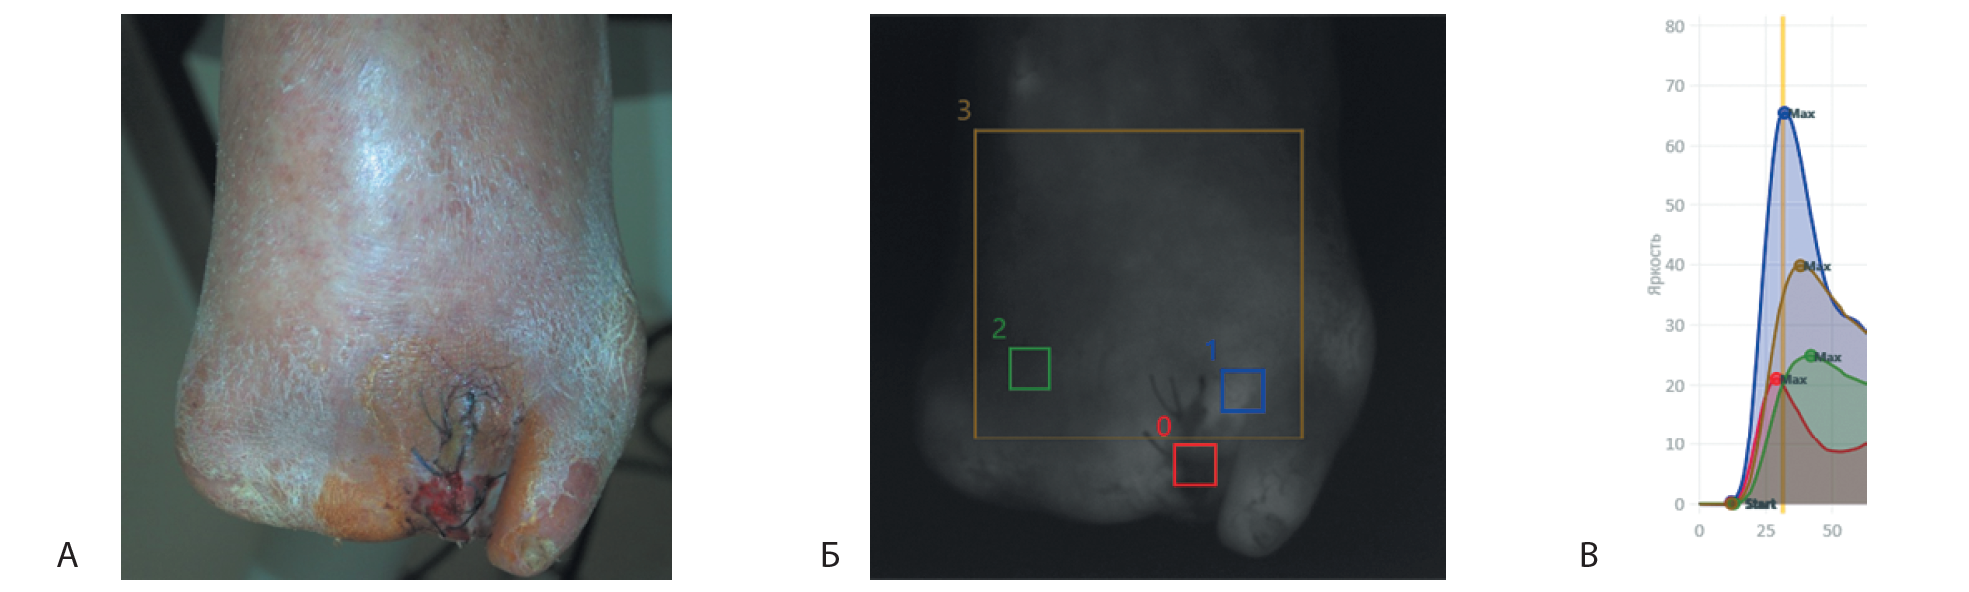

Результаты параметров ФАГ в БИД левой стопы указаны на рис. 2, в табл. 2.

Таблица 2. Результаты флуоресцентной ангиографии в ближнем инфракрасном диапазоне левой стопы у пациента Б. на стадии критической ишемии нижних конечностей

Рис. 2. Результат флуоресцентной ангиографии (ФАГ) в ближнем инфракрасном диапазоне (БИД) левой стопы. А – вид стопы на момент исследования. Б – вид стопы в ходе проведения ФАГ в БИД. Области оценки параметров ФАГ в БИД: 0 – область минимальной флуоресценции; 1 – область максимальной флуоресценции; 2 – область 1-го межпальцевого промежутка; 3 – область исследования большей части стопы. В – диаграмма ФАГ в БИД в зонах интереса 0–3. Tstart (с) – время появления флуоресценции (Istart, юнит) в исследуемой области после внутривенного введения индоцианина зеленого (ИЦЗ); Tmax (с) – время достижения максимальной флуоресценции (Imax, юнит) после внутривенного введения ИЦЗ; Tmax-Tstart (с) – разница во времени достижения Imax и Istart.

Результаты параметров ФАГ в БИД левой стопы в послеоперационном периоде указаны на рис. 5, в табл. 4.

Таблица 4. Результаты флуоресцентной ангиографии в ближнем инфракрасном диапазоне левой стопы у пациента Б. после чрескожной транслюминальной баллонной ангиопластики артерий левой нижней конечности

Рис. 5. Результат параметров флуоресцентной ангиографии (ФАГ) в ближнем инфракрасном диапазоне (БИД) левой стопы в послеоперационном периоде. А – вид стопы на момент исследования. Б – вид стопы в процессе проведения ФАГ в БИД. Области оценки параметров ФАГ в БИД: 0 – область минимальной флуоресценции; 1 – область максимальной флуоресценции; 2 – область 1-го межпальцевого промежутка, 3 – область исследования большей части стопы. В – диаграмма ФАГ в БИД в зонах интереса 0–3. Tstart (с) – время появления флуоресценции (Istart, юнит) исследуемой области после внутривенного введения индоцианина зеленого (ИЦЗ); Tmax (с) – время достижения максимальной флуоресценции (Imax, юнит) после внутривенного введения ИЦЗ; Tmax –Tstart (с) – разница во времени достижения Imax и Istart

Основной целью текущей госпитализации являлось лечение рецидива КИНК левой нижней конечности, формирующей высокий риск ампутации нижней конечности согласно стратификации рисков по классификации WIFI. Диагноз КИНК левой нижней конечности был установлен на основании клинического обследования (боли в стопе, гангрена II пальца левой стопы), тяжесть ишемии подтверждена неинвазивными методами диагностики: уровень ЛАД менее 40 мм рт.ст., ЛПИ менее 0,28, уровень TcpО2 – 7 мм рт.ст. По данным ФАГ в БИД определены временные параметры старта флуоресценции и достижения максимального уровня флуоресценции после внутривенного введения ИЦЗ в различных зонах интереса на стопе (см. рис. 2, см. табл. 2) у пациента на стадии КИНК. После успешной реваскуляризации АНК подтверждено разрешение КИНК согласно результатам неинвазивных методов диагностики ишемии с достижением оптимального уровня оксигенации тканей стопы. По данным результатов проведенного ФАГ в БИД в послеоперационном периоде выявлено сокращение времени появления и достижения максимальной флуоресценции ИЦЗ после его внутривенного введения (см. рис. 5, табл. 4). Подобные результаты проведенных ФАГ в БИД у пациентов с ЗАНК наблюдались в исследованиях зарубежных коллег [7, 8].